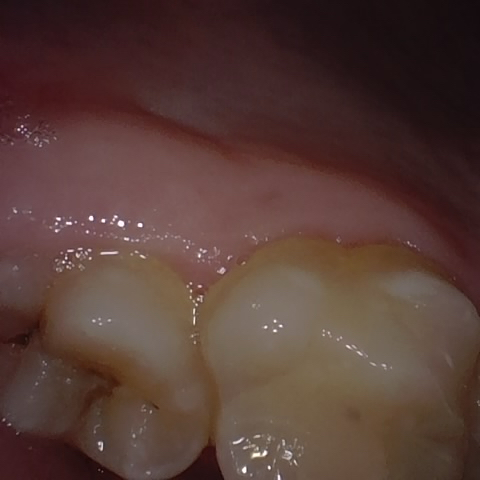

Annotated as "Good"